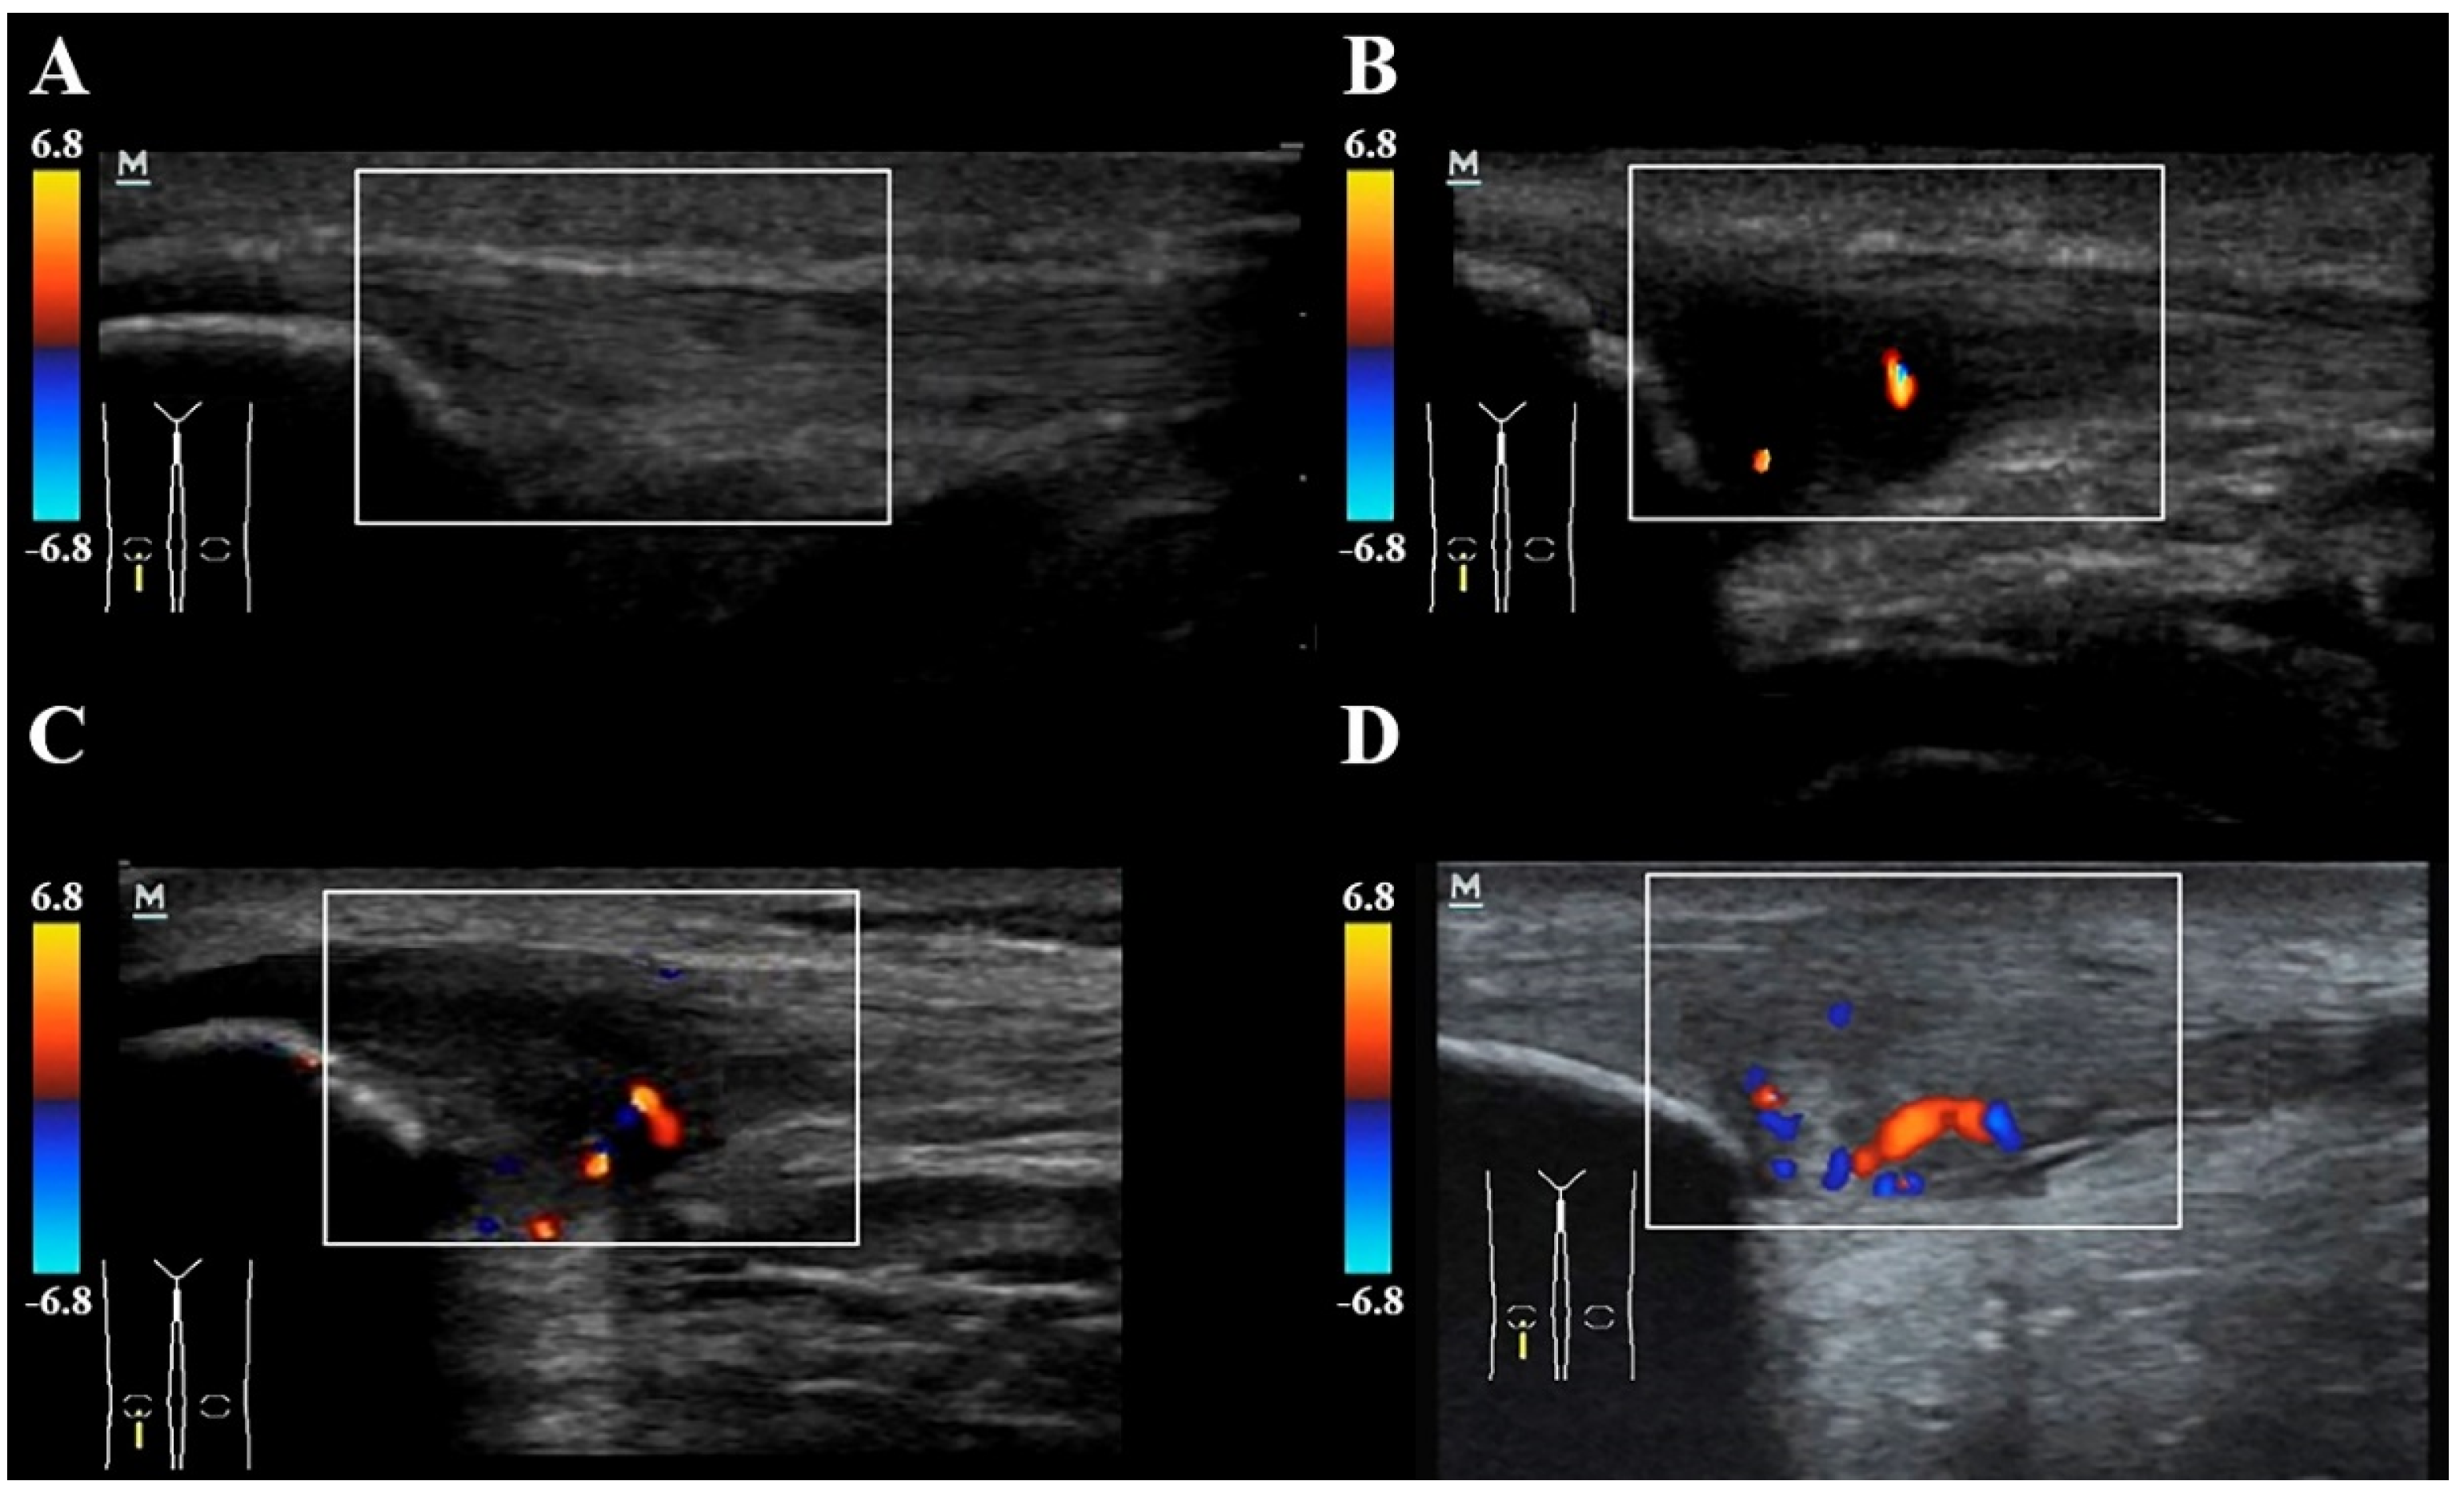

2.4. Neovascularization and Doppler Assessment of the Patellar Tendon

- Boesen, M.I.; Boesen, A.; Koenig, M.J.; Bliddal, H.; Torp-Pedersen, S. Ultrasonographic Investigation of the Achilles Tendon in Elite Badminton Players Using Color Doppler. Am. J. Sports Med. 2006, 34, 2013–2021. [Google Scholar] [CrossRef]

- Gisslen, K.; Alfredson, H.; Peers, K. Neovascularisation and pain in jumper’s knee: A prospective clinical and sonographic study in elite junior volleyball players * Commentary. Br. J. Sports Med. 2005, 39, 423–428. [Google Scholar] [CrossRef]

| Vascularization grading system Grade 0 Grade I Grade II Grade III Grade IV | 20; 100% - - - - | 6; 30% 10; 50% 4; 20% - - | |